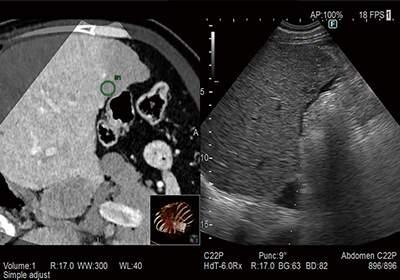

治療をサポートする

「Real-time Virtual Sonography」搭載(オプション)

CT・MRI・超音波診断装置のボリュームデータから作成したMPR画像を超音波画像とリアルタイムで同期させる機能です。超音波検査だけでは発見しづらい小さな病変の発見や,治療部位の決定など安全かつ正確な治療への貢献が期待されます。